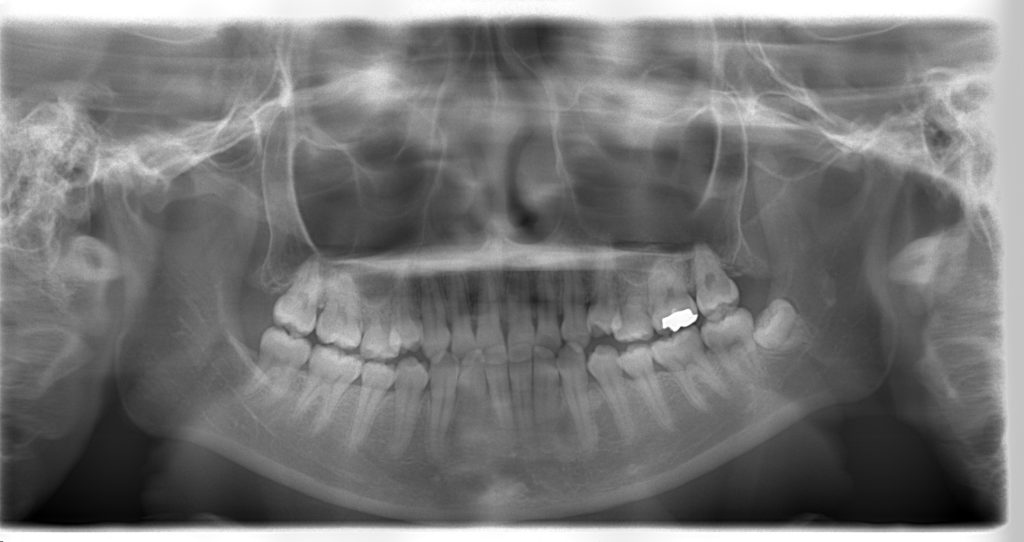

レントゲン↓

治療前

治療後

セファロ(横顔)のレントゲンを見ていただくと分かりやすいですが、出っ歯が治っております!!!Eラインがいい感じになりました。